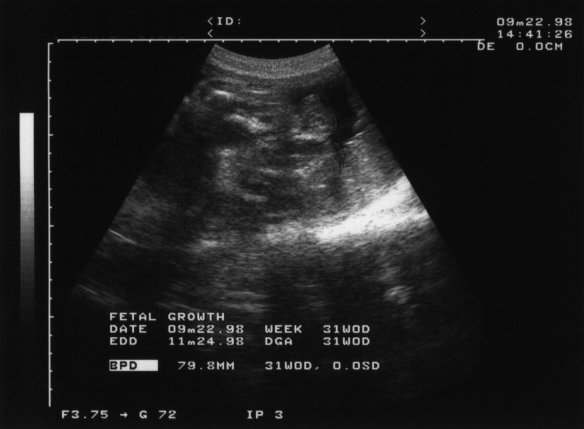

98年9月22日(妊娠31週1日)

やはり入りきらなくて何が写っているのか分らない.

奥さんからは「エコー好きやなぁ」と言われた. お腹の大きさ見てても良く分らないので,何が写っているのか分らなくても見てみたいって言うのが人情ってやつですよネェ〜.

どうも今回のエコーは,「○ん○ん」と「たまたま」が写っているらしい. そう. ほとんど男の子で間違いないらしい. 私は,1人目だから元気で生れてさえくれれば,どちらでも良かったんだけど,奥さんは喜んでいた. 私もなぜかホッとした.